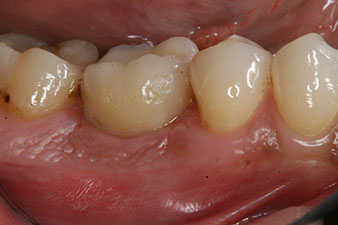

Après cicatrisation des tissus mous, la stabilité de l’implant a été mesurée une nouvelle fois avant la pose de la restauration prothétique.

Les deux valeurs étaient pratiquement inchangées, situées entre la plage moyenne et la plage haute - la valeur la plus basse étant toujours utilisée comme valeur de référence qui détermine le traitement.

Par conséquent, il a été possible d’enregistrer une ostéo-intégration réussie et une stabilité biologique correcte, permettant également de prendre une empreinte durant la même séance.

Les dernières photos montrent la couronne composite monolithique retenue par une vis une fois mise en place et la radio de contrôle (Fig. 9 et 10) (6).